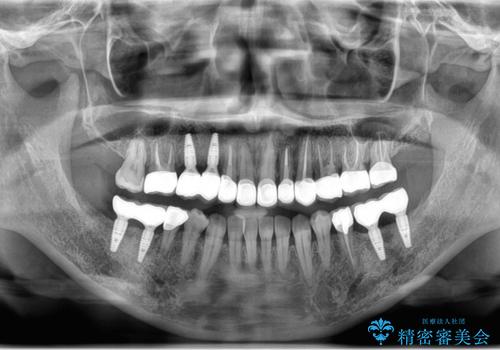

当院に初診来院時は左下の奥歯に重度歯周病が見られ、高度に骨吸収している状態でした。

抜歯後、高度に骨の吸収が生じたため骨の造成を行ったのちにインプラントを2本埋入、4ヶ月後に2次手術(歯ぐきの移植)を行いました。

骨・歯ぐきの環境を整えたのちに、最終的なかぶせものを作製していきます。

今回はジルコニアカスタムアバットメント、オールセラミックジルコニアクラウンで最終的な被せ物を作製しました。